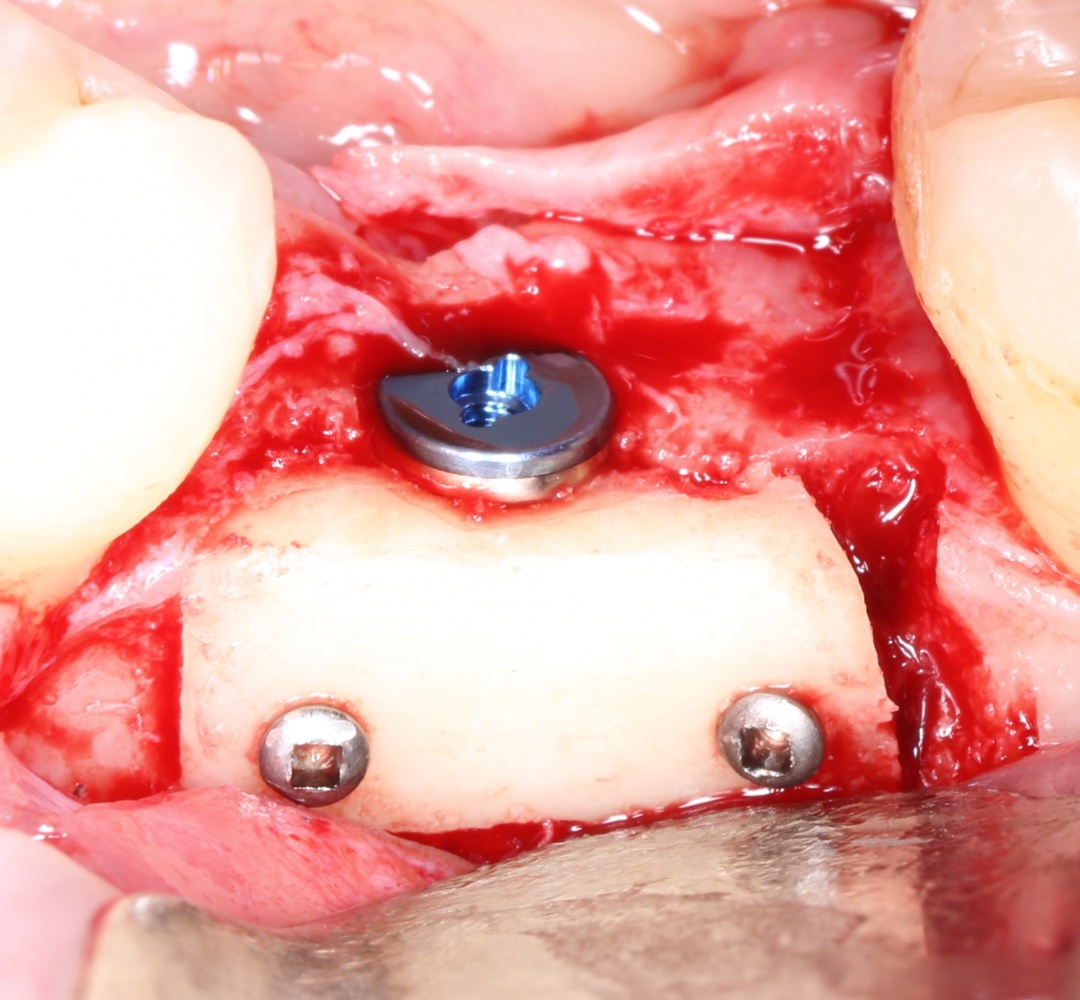

Изоляция области аутографта и имплантатов барьерной мембраной.

Конкретно в этом клиническом случае между костным аутотрансплантатом, ложем и имплантатами есть пустое пространство. Если его не изолировать от мягких тканей, они прорастут и осложнят интеграцию аутографта. Поэтому я решил перекрыть костный блок барьерной мембраной, пусть это делает хирургическую операцию немного дороже.

— я использовал барьерную мембрану Geistlich Bio-Gide, которая имеет две разные поверхности: с одной стороны она рыхлая «адгезивная», с другой — гладкая и прочная. Как укладывать — на результат не влияет, но в плане удобства рыхлую поверхность мы «приклеиваем» к тому, на чем требуется барьерную мембрану удержать. В данном случае хотелось бы удержать её на костной поверхности — следовательно, мы укладываем её рыхлой поверхностью к кости.

— ты знаешь, что барьерная мембрана может выполнять две функции, каркасную и изолирующую. Первая функция требует обязательной фиксации и натяжения, вторая — нет. В нашем случае «каркасом» регенерата является костный блок, а барьерная мембрана нужна только для изоляции. Поэтому она не требует натяжения и фиксации пинами.

После я внимательно проверил, что костный блок и имплантаты полностью перекрыты. Теперь рану можно ушивать.